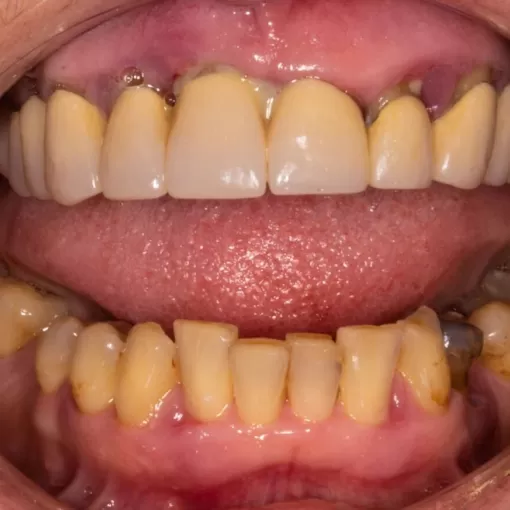

Пациентка, 49 лет. Пародонтологическое лечение

Пациентка, 49 лет. Многократно обращалась по месту жительства к стоматологам и проходила курсы местного лечения и антибиотикотерапии у пародонтолога, но процесс прогрессировал. Пришла на консультацию в полном отчаянии и с рекомендациями удалить все зубы для изготовления съёмных протезов.